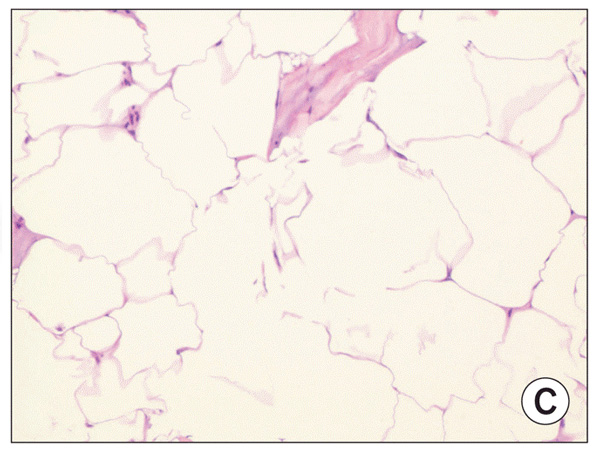

Многие сморщенные адипоциты видны в жировых слоях с отсутствующей воспалительной клеточной инфильтрацией (х40)

ядерная фрагментация между адипоцитами

Несколько апоптотических ядер демонстрируют ядерную фрагментацию между адипоцитами (х100)